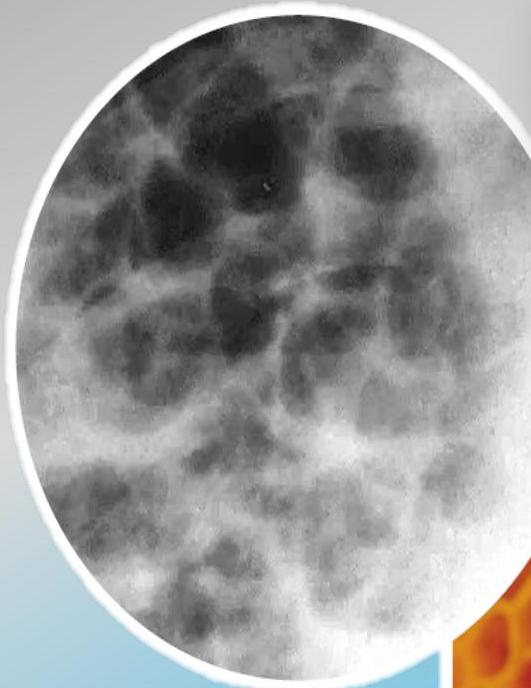

Radiographic Findings (Chest X-ray)

Conglomerating cysts of varying size and wall thickness. “Honeycomb” sign.